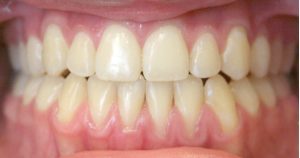

Before and After photos: Crossbite Treatment